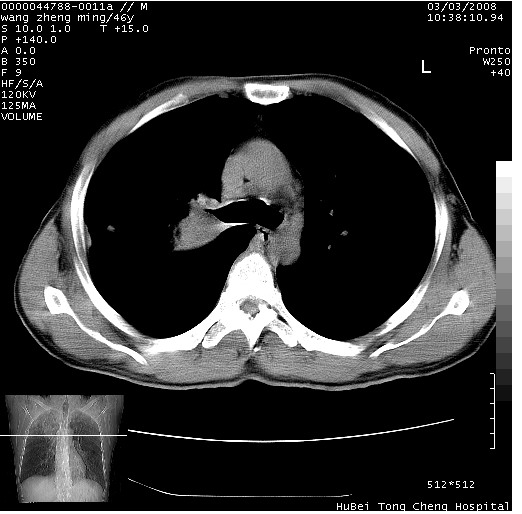

以下是引用卜一在2008-3-22 1:37:00的发言:[br]右肺实质性肿块,边缘不整,明显见毛刺征 分叶征及胸膜凹陷征,右上叶支气管明显变窄,远端散在的片状 斑片状实变影。另:左肺门较大肿块,支气管受累 变窄,远侧见阻塞性肺炎。纵隔内见肿大淋巴结。多考虑:右肺周围性肺癌伴左肺门 纵隔淋巴结转移!